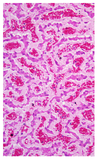

What will you see microscopically in a patient with jaundice?

- Do not see pigment in jaundiced tissues!

- Exception: severe cholestatic (obstructive bile flow) liver

- Yellow-brown intracellular (hepatocytes, kupffer cells) or extracellular pigement (bile canalliculi)